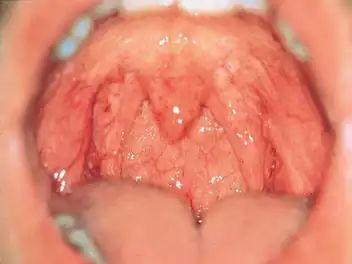

慢性单纯性咽炎怎么治?

第一:阴虚肺燥 症状:咽喉干疼、灼热,多言之后症状加重,干咳少痰,口干不欲多饮,午后及黄昏时症状明显。咽部充血呈暗红色,粘膜干燥,或有淋巴滤泡增生。舌红,苔薄,脉细数。 [治法]滋阴清热,清利咽窍。 [方药]养阴清咽汤或养阴清肺汤合二至丸加减:南沙参16克,玄参16克,百合16克,冬桑叶12克,炙枇杷叶12克,西藏青果7克,五味子7克,生甘草7克。咽异物感明显者加绿萼梅7克,橘络7克;脉络曲张明显者加丹参12克,丝瓜络7克。

第二:痰热蕴结 症状:咽喉不适,因受凉、疲劳,多言之后症状较重。咳嗽,咯痰粘稠,口渴喜饮。咽粘膜充血呈深红色,肥厚,有黄白色分泌物附着。舌红,苔黄腻,脉滑数, [治法]养阴清热,化痰活血,舒利咽窍。 [方药]清痰润咽汤或养阴清肺汤合消瘰丸加减:全瓜萎16克,川贝母16克,生牡蛎16克,玄参16克,南沙参16克,凤凰衣12克,木蝴蝶7克,西藏青果7克,生甘草7克,红花7克。咽刺痛甚者加赤芍药12克,丹参12克,玫瑰花7克,小瘰丛生严重者加三棱7克,莪术7克,海浮石16克。